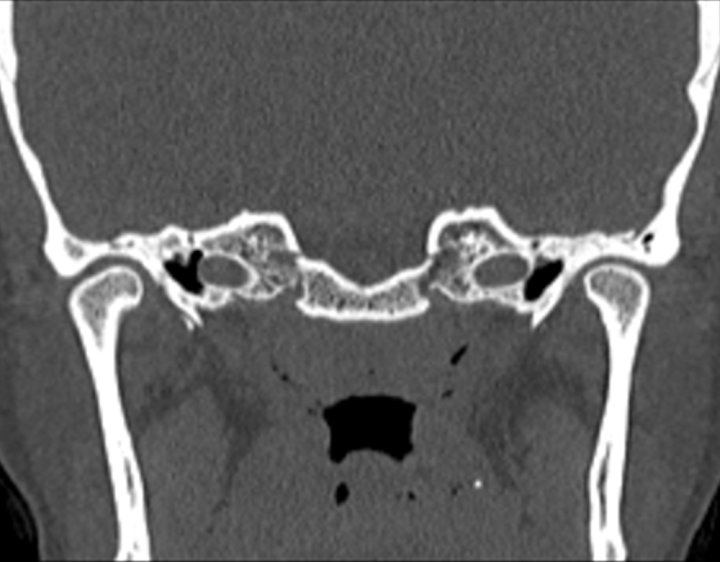

Click any image for labels.